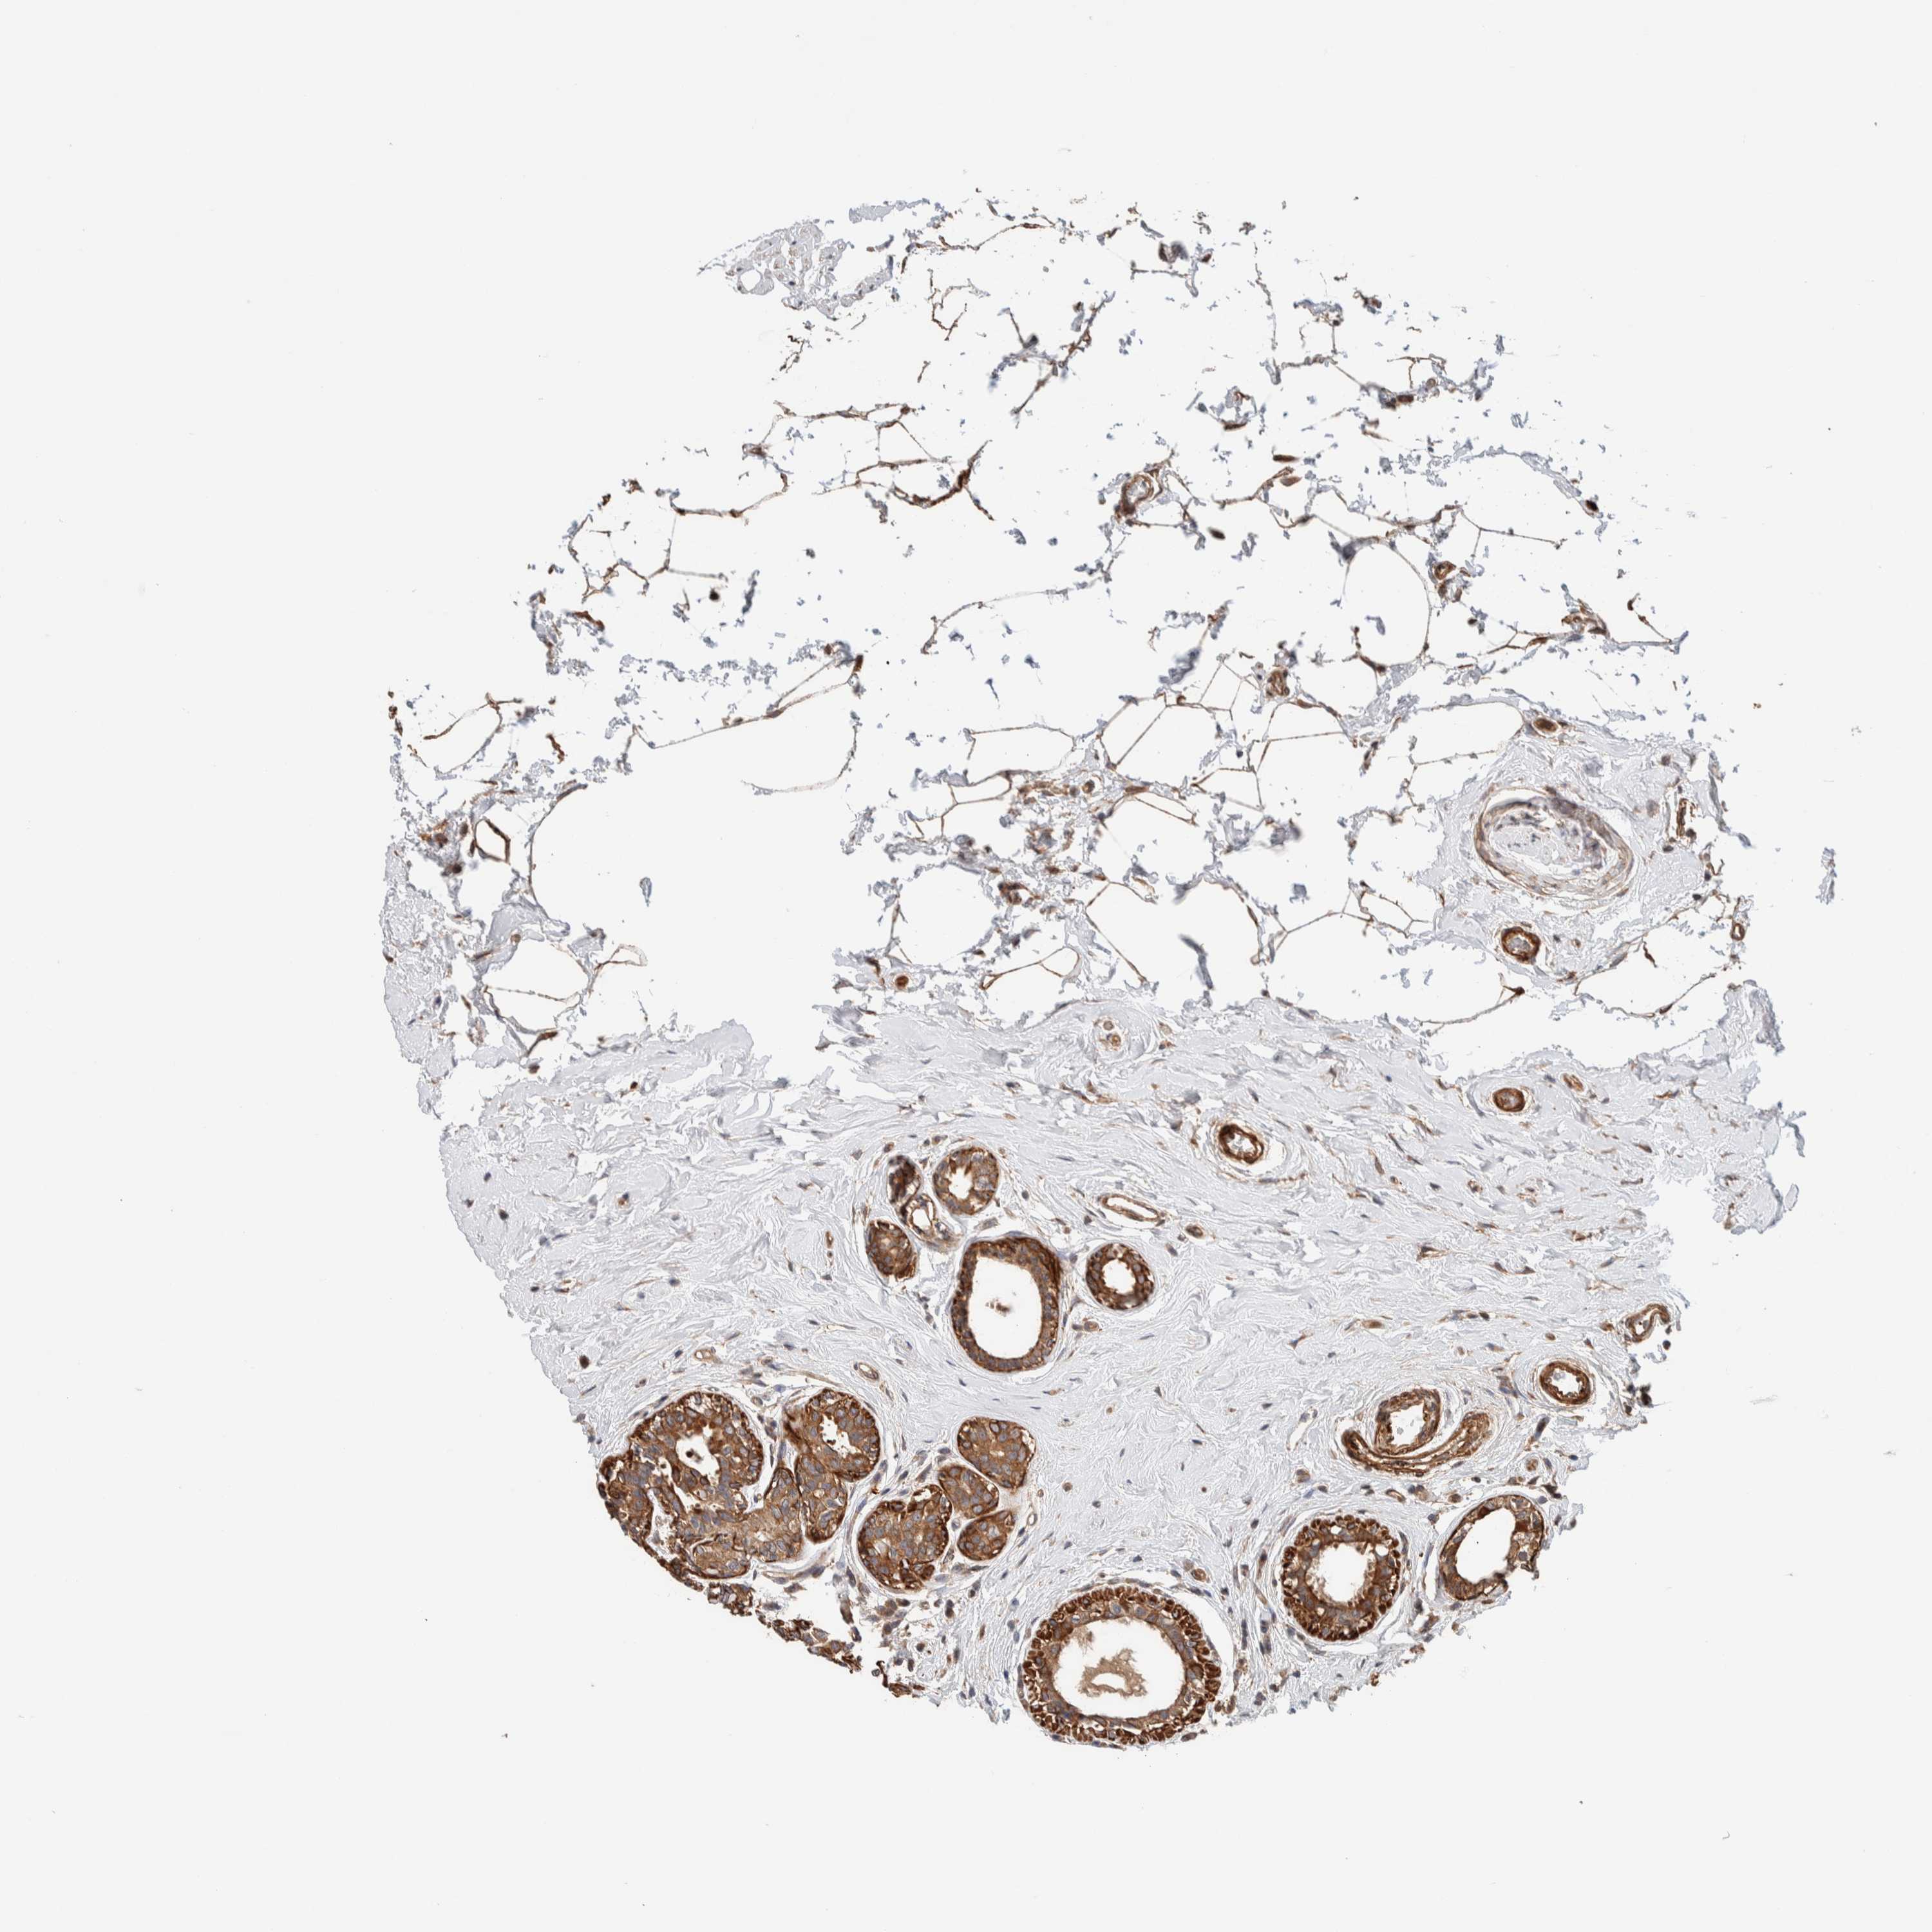

CANCER BREAST CANCER Show tissue menu

BRCA TCGA BRCA VALIDATION PROTEIN EXPRESSION